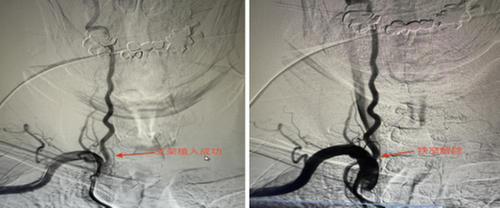

據(jù)悉,這是該院神經(jīng)內(nèi)科第一例椎動(dòng)脈狹窄支架植入術(shù),患者術(shù)后愈合極好。該手術(shù)為四級(jí)手術(shù),它的成功標(biāo)志著醫(yī)院卒中中心救治急危重癥患者的技術(shù)水平再上新臺(tái)階。

1月26日,尹大爺因“頭暈、聲嘶,伴有步態(tài)不穩(wěn)及飲水嗆咳2天”到市中區(qū)人民醫(yī)院就診,考慮為,急性腦干梗死。醫(yī)院立即啟動(dòng)卒中綠色通道,急診行頭顱MRI+DWI+MRA提示,急性腦干梗死(延髓左份)。其間,考慮到尹大爺高齡和患有高血壓等基礎(chǔ)疾病,醫(yī)院立即組織開(kāi)展MDT討論,制定了詳細(xì)的血管內(nèi)治療手術(shù)方案,征得患者及家屬同意后,神經(jīng)內(nèi)科團(tuán)隊(duì)在局麻下進(jìn)行右側(cè)椎動(dòng)脈支架植入術(shù),手術(shù)順利,術(shù)后復(fù)查頭頸部CTA提示右側(cè)椎動(dòng)脈起始部狹窄解除。